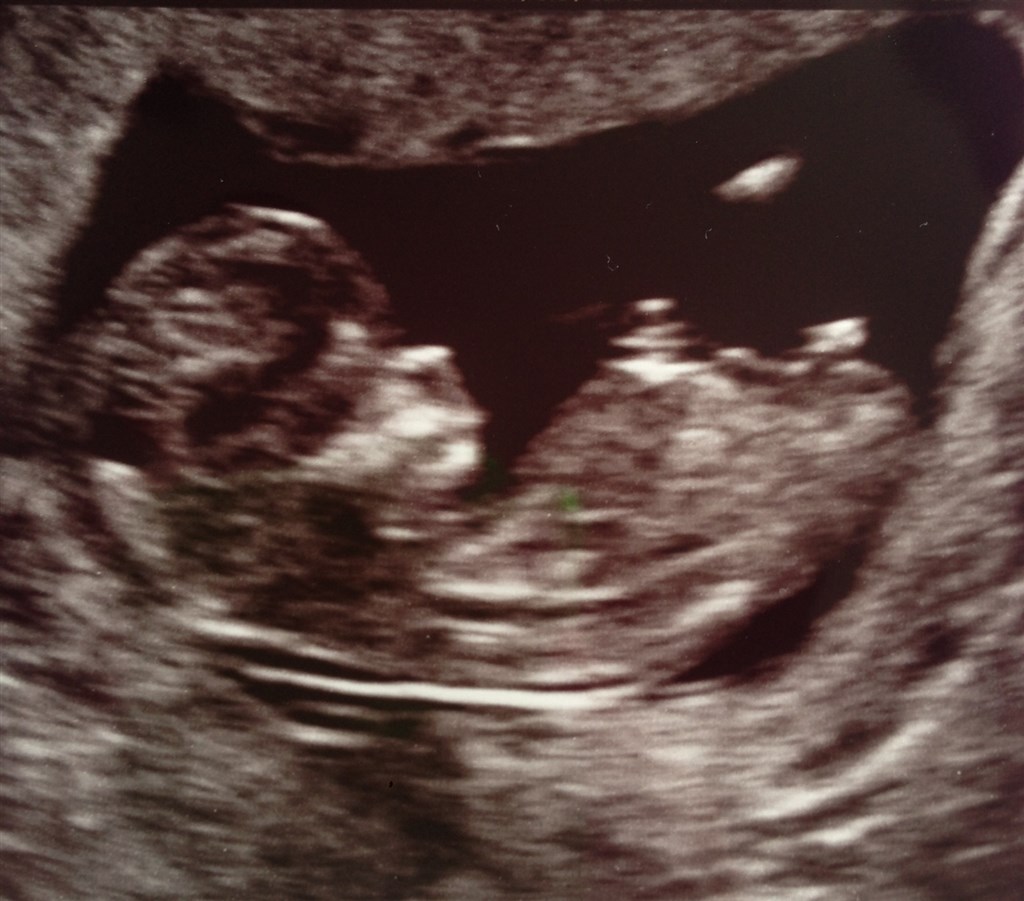

Så har vi været til NF. Hold da op, hvor var jeg nervøs! Jeg var lige ved at besvime, da hun satte scanneren på min mave, men heldigvis så vi med det samme det lille foster, som var noget større end sidst.

Alt så helt perfekt ud. Hjertet slog derudad med ca. 166 slag i minuttet. Der var to arme og ben og man kunne ane både fingrene og tæerne.

Den lille var 5,5 cm, og min termin blev rykket til d. 29. november 2013.

Her er lige et par billeder af vores lille blyp <3

Vedhæftede fotos (klik for at se i fuld størrelse)